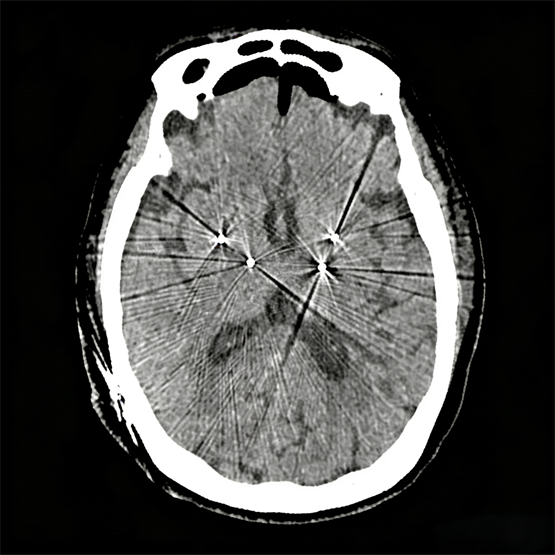

▲DBS术后电极位置验证CT图

手术室内,团队配合默契,整个手术过程非常繁琐,分别定位4个靶点,反复调整8次头架,验证32次靶点坐标,同时再加上术中电生理的监测,电极测试等,全部工序加起来接近200道,每一步都必须保证精准,不容有半点差池。当四根电极的植入位置在术中影像上与术前计划完美重合时,所有人都松了一口气,这标志着这台开创性手术取得了关键成功。